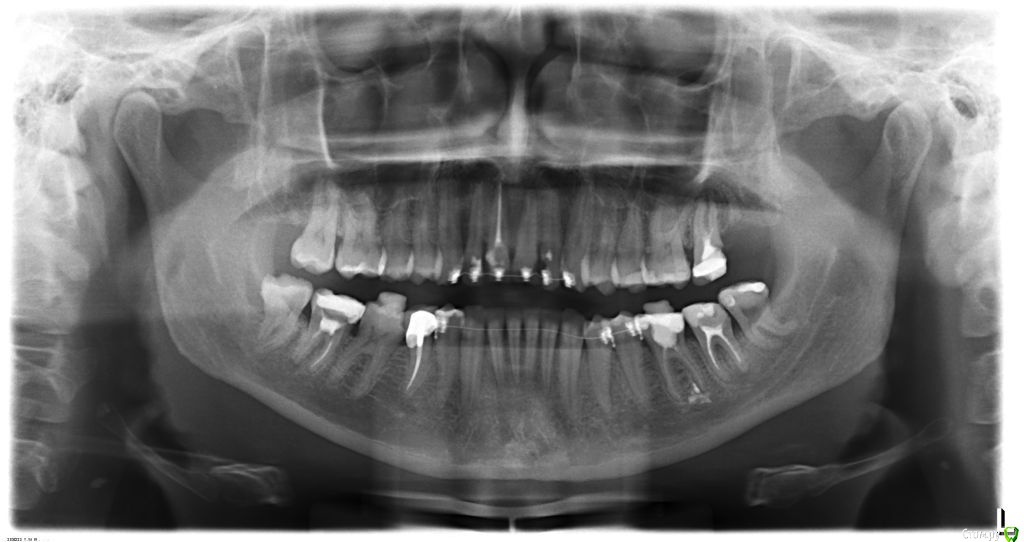

ol"ga Опубликовано 15 августа, 2015 Автор Поделиться Опубликовано 15 августа, 2015 (изменено) Вот еще кт левого и правого внчс, и фото улыбки Изменено 15 августа, 2015 пользователем ol"ga Ссылка на комментарий

Yana guapa Опубликовано 15 августа, 2015 Поделиться Опубликовано 15 августа, 2015 я не вижу у ВАс асимметрии лица, асимметрии верхней челюсти. А вот нижняя челюсть смещена влево, (это видно по ОПТГ и фото), вследствие чего произошло смещение дискав таких случаях обычно1. выравнивают зубные ряды ( с удалением восьмерок) 2. ставят нижнюю челюсть в правильное положение (различными способами, специальные пружины, эластики, форсус, твин форс и т.д.) каждый врач сам для себя выберает, что ему удобнее п.с. похоже что вверху слева ВАм удаляли восьмерку, нго оставили 1 корень. Ссылка на комментарий

ol"ga Опубликовано 15 августа, 2015 Автор Поделиться Опубликовано 15 августа, 2015 (изменено) Ой, забыла сказать, оптг делала еще с лингвальными брекетами, там на каждом снимке есть дата, это снимок до возникшей проблемы с внчс и асимметрии лица. И фото все подписаны до ортодонтического лечения и после, извиняюсь, что не совсем внятно изложила информацию. Изменено 15 августа, 2015 пользователем ol"ga Ссылка на комментарий

Yana guapa Опубликовано 15 августа, 2015 Поделиться Опубликовано 15 августа, 2015 по снимкам - все итак понятно, без подписей.по "щечкам" - Вам скуловые кости никто не двигал, мягкие ткани ортодонт тоже не перемещал, так что это не в юрисдикции ортодонта. вот поворот нижней челюсти - это да, это видно и этим можно заниматься Ссылка на комментарий

Yana guapa Опубликовано 16 августа, 2015 Поделиться Опубликовано 16 августа, 2015 . Не смогли, сказали что могут повредить гайморову пазуху, удалят потом, когда корень капсулируетя и можно будет за него схватиться.по мне- самый обычный корень, далеко от пазухи. удаляйтк его и остальные восьмерки.а затем ставьте НЧ в правильное положение в таких случаях обычно1. выравнивают зубные ряды ( с удалением восьмерок) 2. ставят нижнюю челюсть в правильное положение (различными способами, специальные пружины, эластики, форсус, твин форс и т.д.) каждый ОРТОДОНТ сам для себя выберает, что ему удобнее Ссылка на комментарий